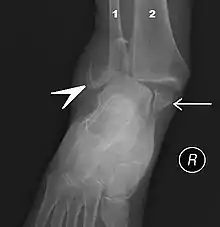

![]() | |

| Fracture of both sides of the ankle with dislocation as seen on anteroposterior X-ray. (1) fibula, (2) tibia, (arrow) medial malleolus, (arrowhead) lateral malleolus | |